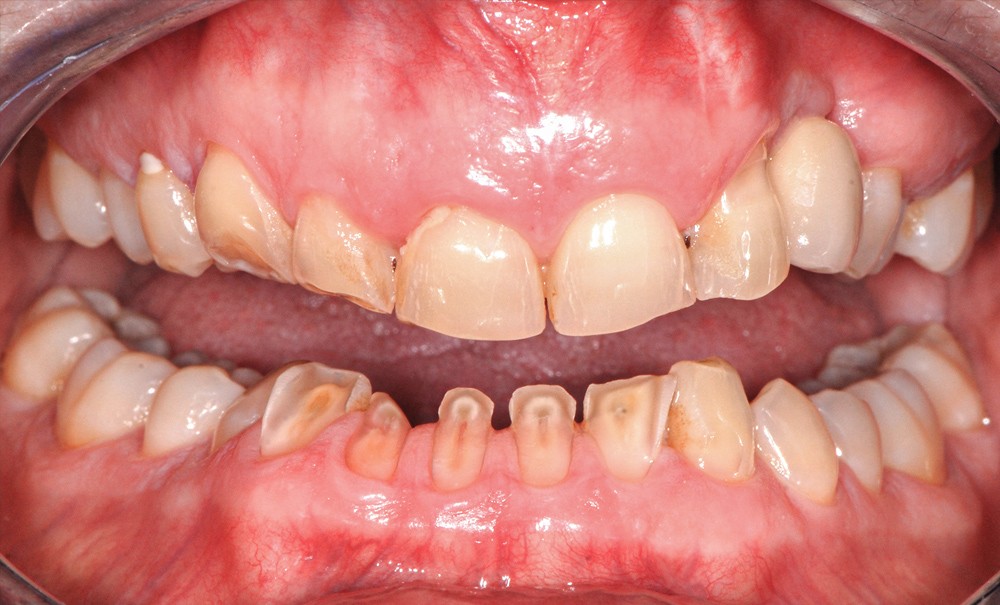

- l’usure particulière des dents du bloc incisivo-canin mandibulaire (fig. 2) ;

Certaines dents antérieures mandibulaires sont réduites pratiquement jusqu’à la…